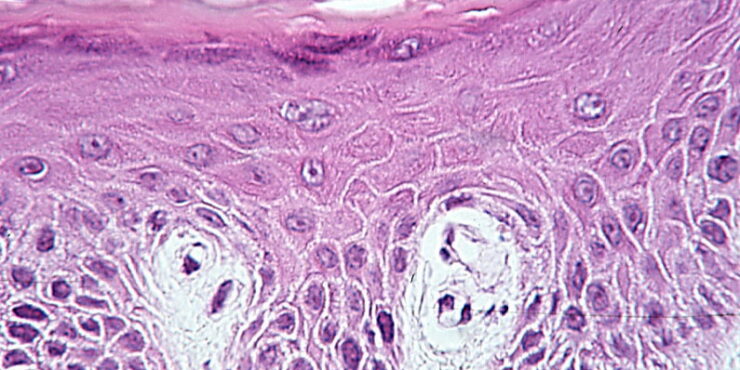

Targetoid hemosiderotic hemangioma =وعاؤوم دموي هيموسيدريني هدفي الشكل